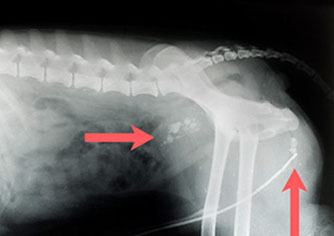

Älterer Hund mit massiver Spondylose 4. Grades mit Brückenbildung